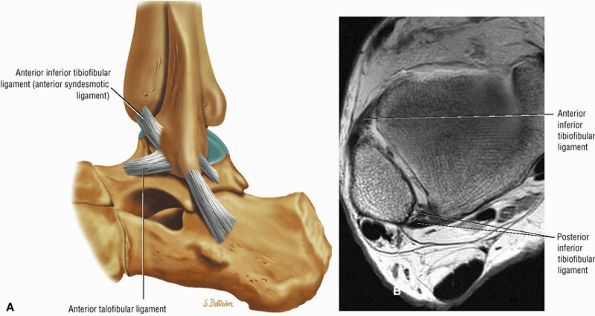

The syndesmotic ligaments consist of the anterior syndesmotic or anterior inferior tibiofibular ligament and the posterior syndesmotic or posterior inferior tibiofibular ligament, the interosseous membrane, and the transverse tibiofibular ligament.

The transverse tibiofibular ligament represents the posterior labrum of the ankle and projects inferior to the posterior tibial margin.

FIGURE 5.59 ● (A) The inferior tibiofibular joint is a fibrous joint. (B) Arthroscopic view of the right ankle demonstrates the syndesmotic ligament and the trifurcation. The trifurcation includes the fibula in the background with the tibia superior and the talus inferior. Approximately 20% of the ligament is intra-articular, and it runs at a 45° angle from the tibia to the fibula.